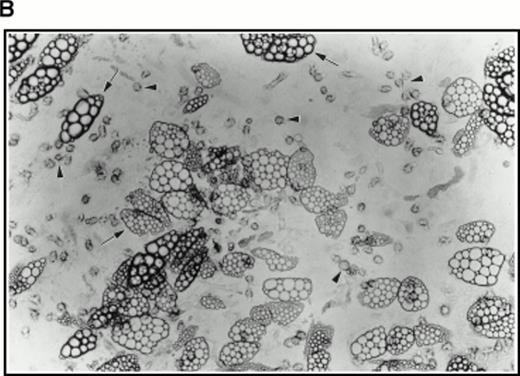

Very few cells survived this procedure. Indeed, as assayed by Trypan blue staining of a small sample, all visible cells were found to be nonviable. However, when used to initiate long-term cultures on preformed, irradiated stroma, this population of cells proved very active in establishing hematopoiesis as evidenced by extensive lipid deposition and characteristic “cobblestone” areas (Fig 4B).

(A) Selection of quiescent bone marrow cells using 5-FU. Bone marrow mononuclear cells were incubated for 7 days in IMDM either supplemented with IL-3, SCF, and 5-FU to kill dividing cells (right-hand panels) or not (left-hand panels). At 4 days of incubation an aliquot was spun onto microscope slides and stained with Wright’s stain (top panels). Twenty-four hours before harvesting, 3H thymidine was added to the cultures. Following 7 days incubation cells were obtained and spun onto microscope slides. The slides were dipped in photographic emulsion and exposed for 7days before being developed, counterstained with Wright’s stain, and visualized under the light microscope (middle panels). (Bottom panels) Cells as above, but stained with antibody to c-kit and viewed under fluorescence. (B) Long-term culture. 5-FU–selected cells were plated on monolayers of bone marrow derived fibroblast as described in Materials and Methods and used to initiate long-term bone marrow cultures. The arrows show areas of extensive lipid deposition characteristic of these types of culture. Arrowheads identify “cobblestone areas,” clusters of developing hematopoietic cells.